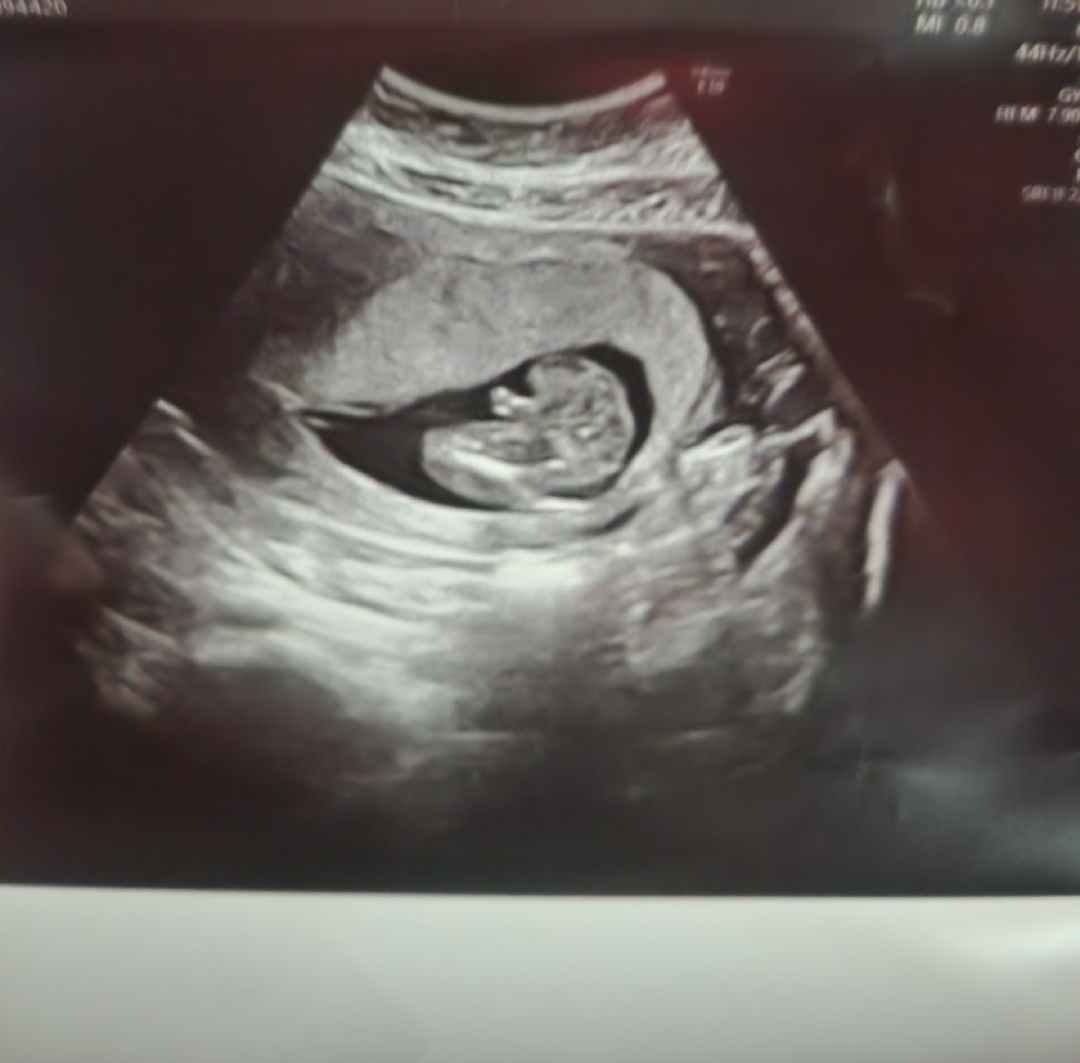

17주차입니다.정확한 성별을 병원서 말을안해주네요

난임병원이라 그런건지 성별을 확실히알려주질않고 저보러 판단하래요.. 아들맞죠?이정도면?..

감사해요..ㅋ그래도 저게진짜 고추인지 다리인지 잘모르겠는거에요..병원서는 저보러 판단하라고하고ㅜㅋ